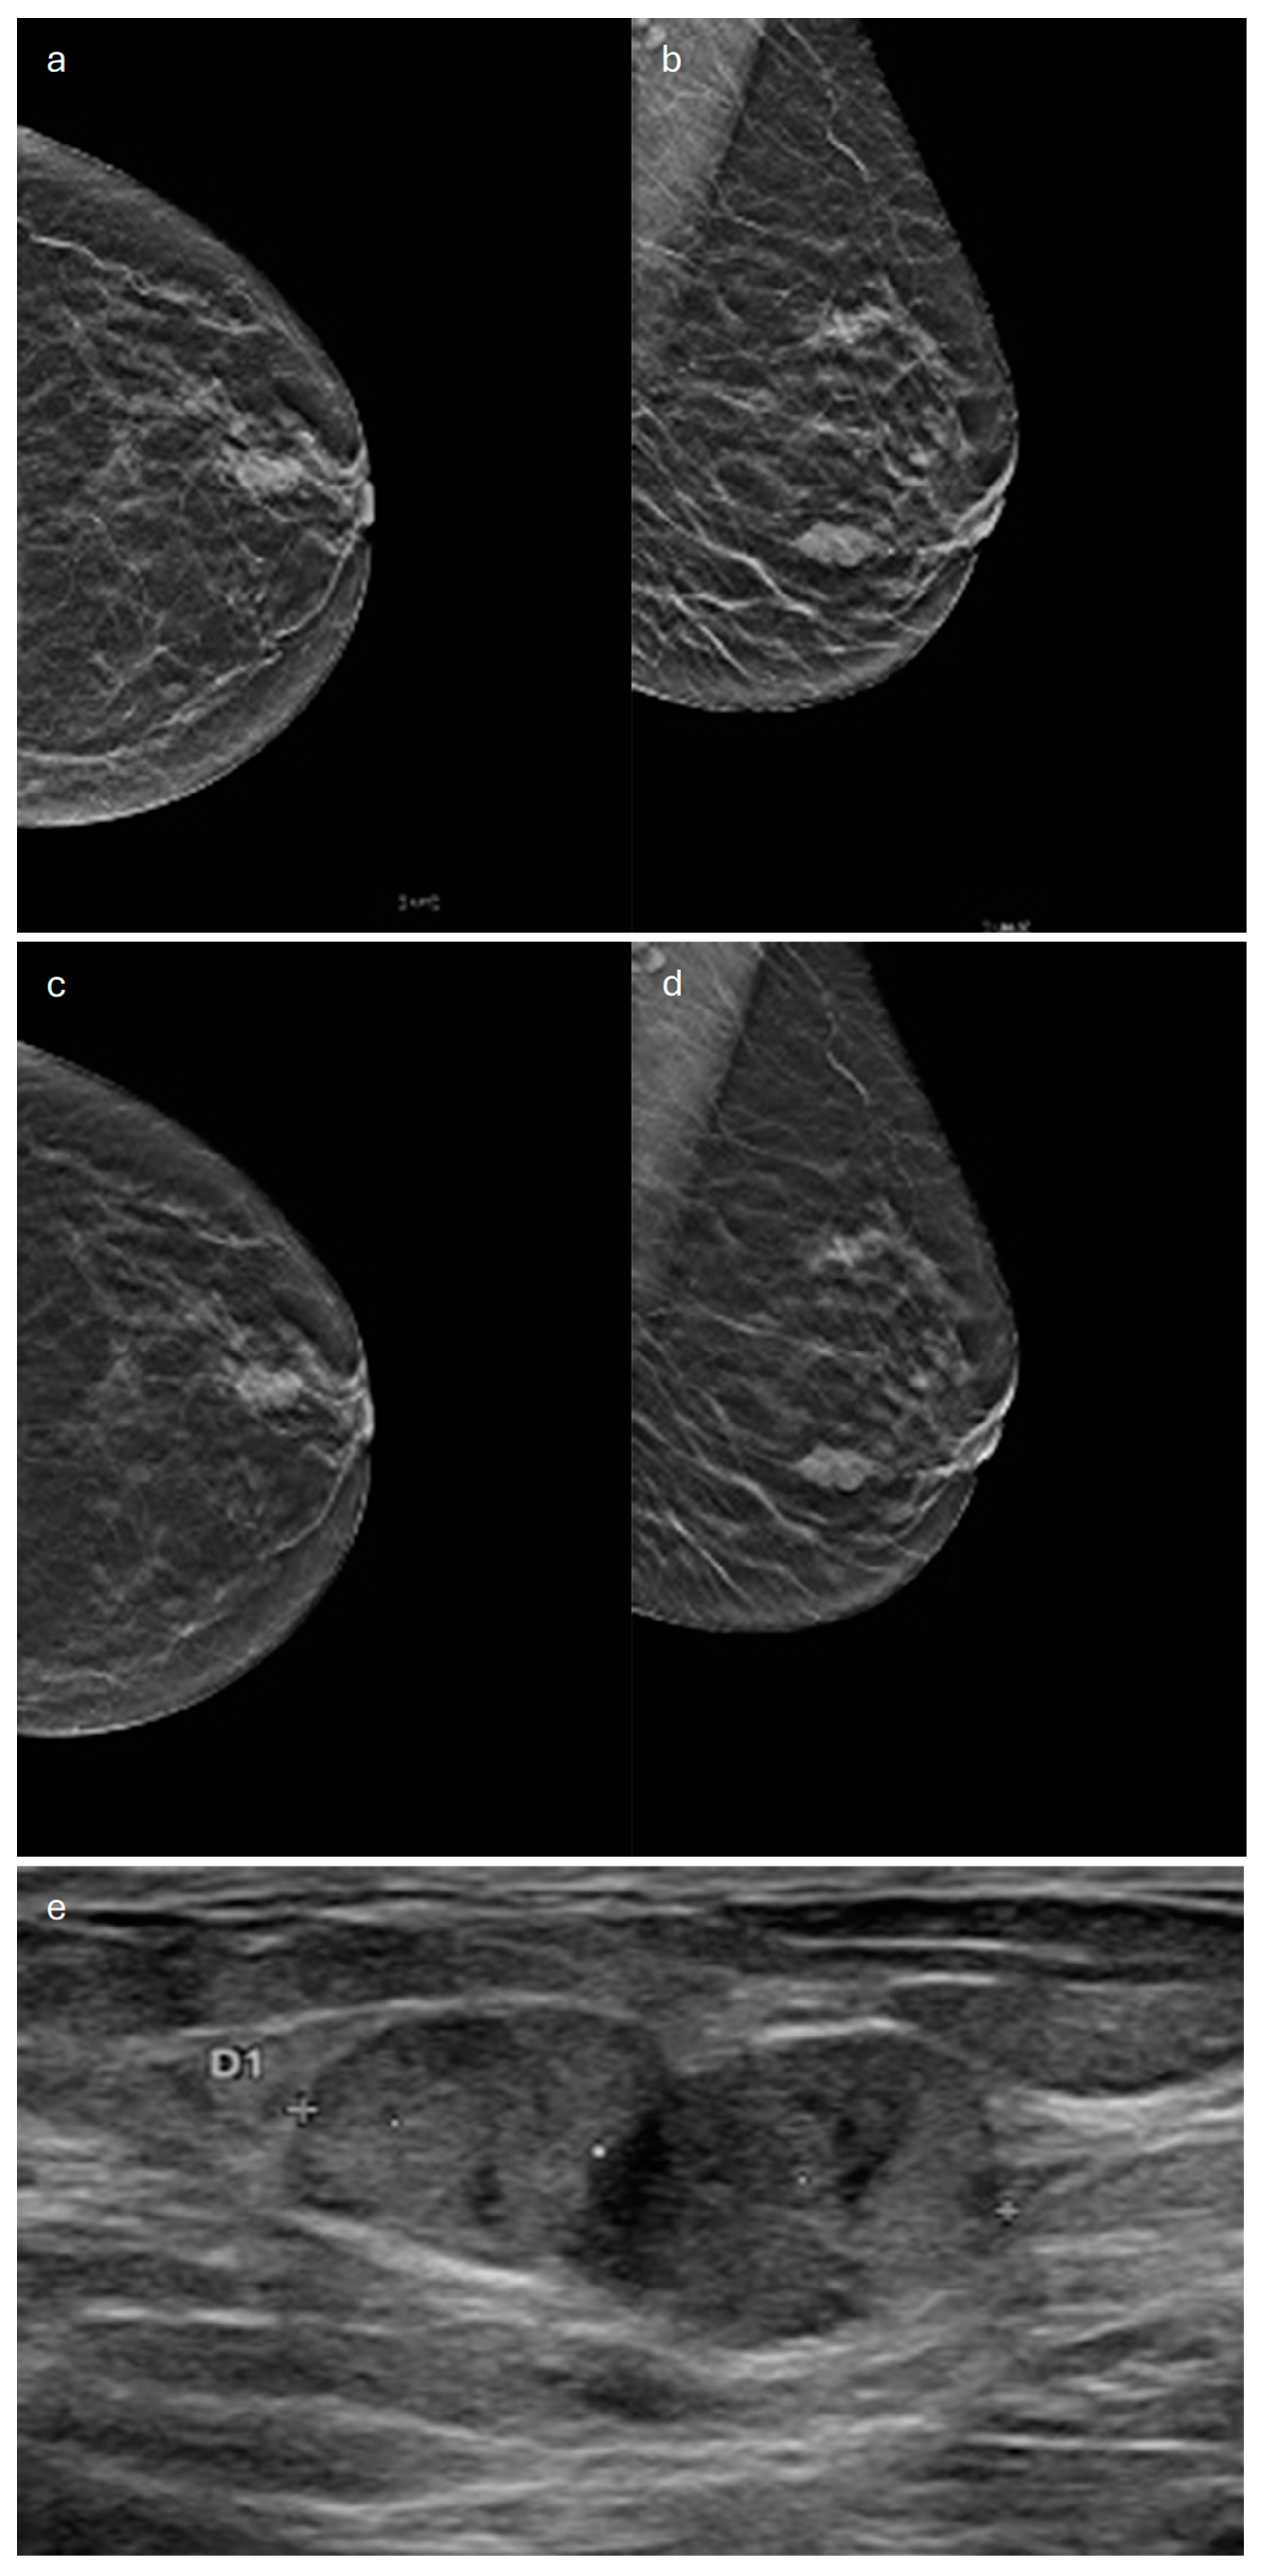

3. Tubular